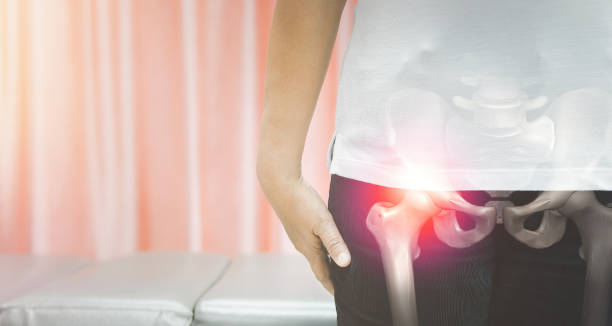

골반통증은 많은 사람들이 겪는 건강 문제 중 하나입니다. 장시간 앉아있거나 일을 많이 하다보면 골반 주변 근육이 약해지고 불균형해지는 경우가 많아 골반통증이 발생할 수 있습니다.

이런 골반통증의 경우 근육이 약해지거나 자세불량 등 다양한 이유가 있는데요.